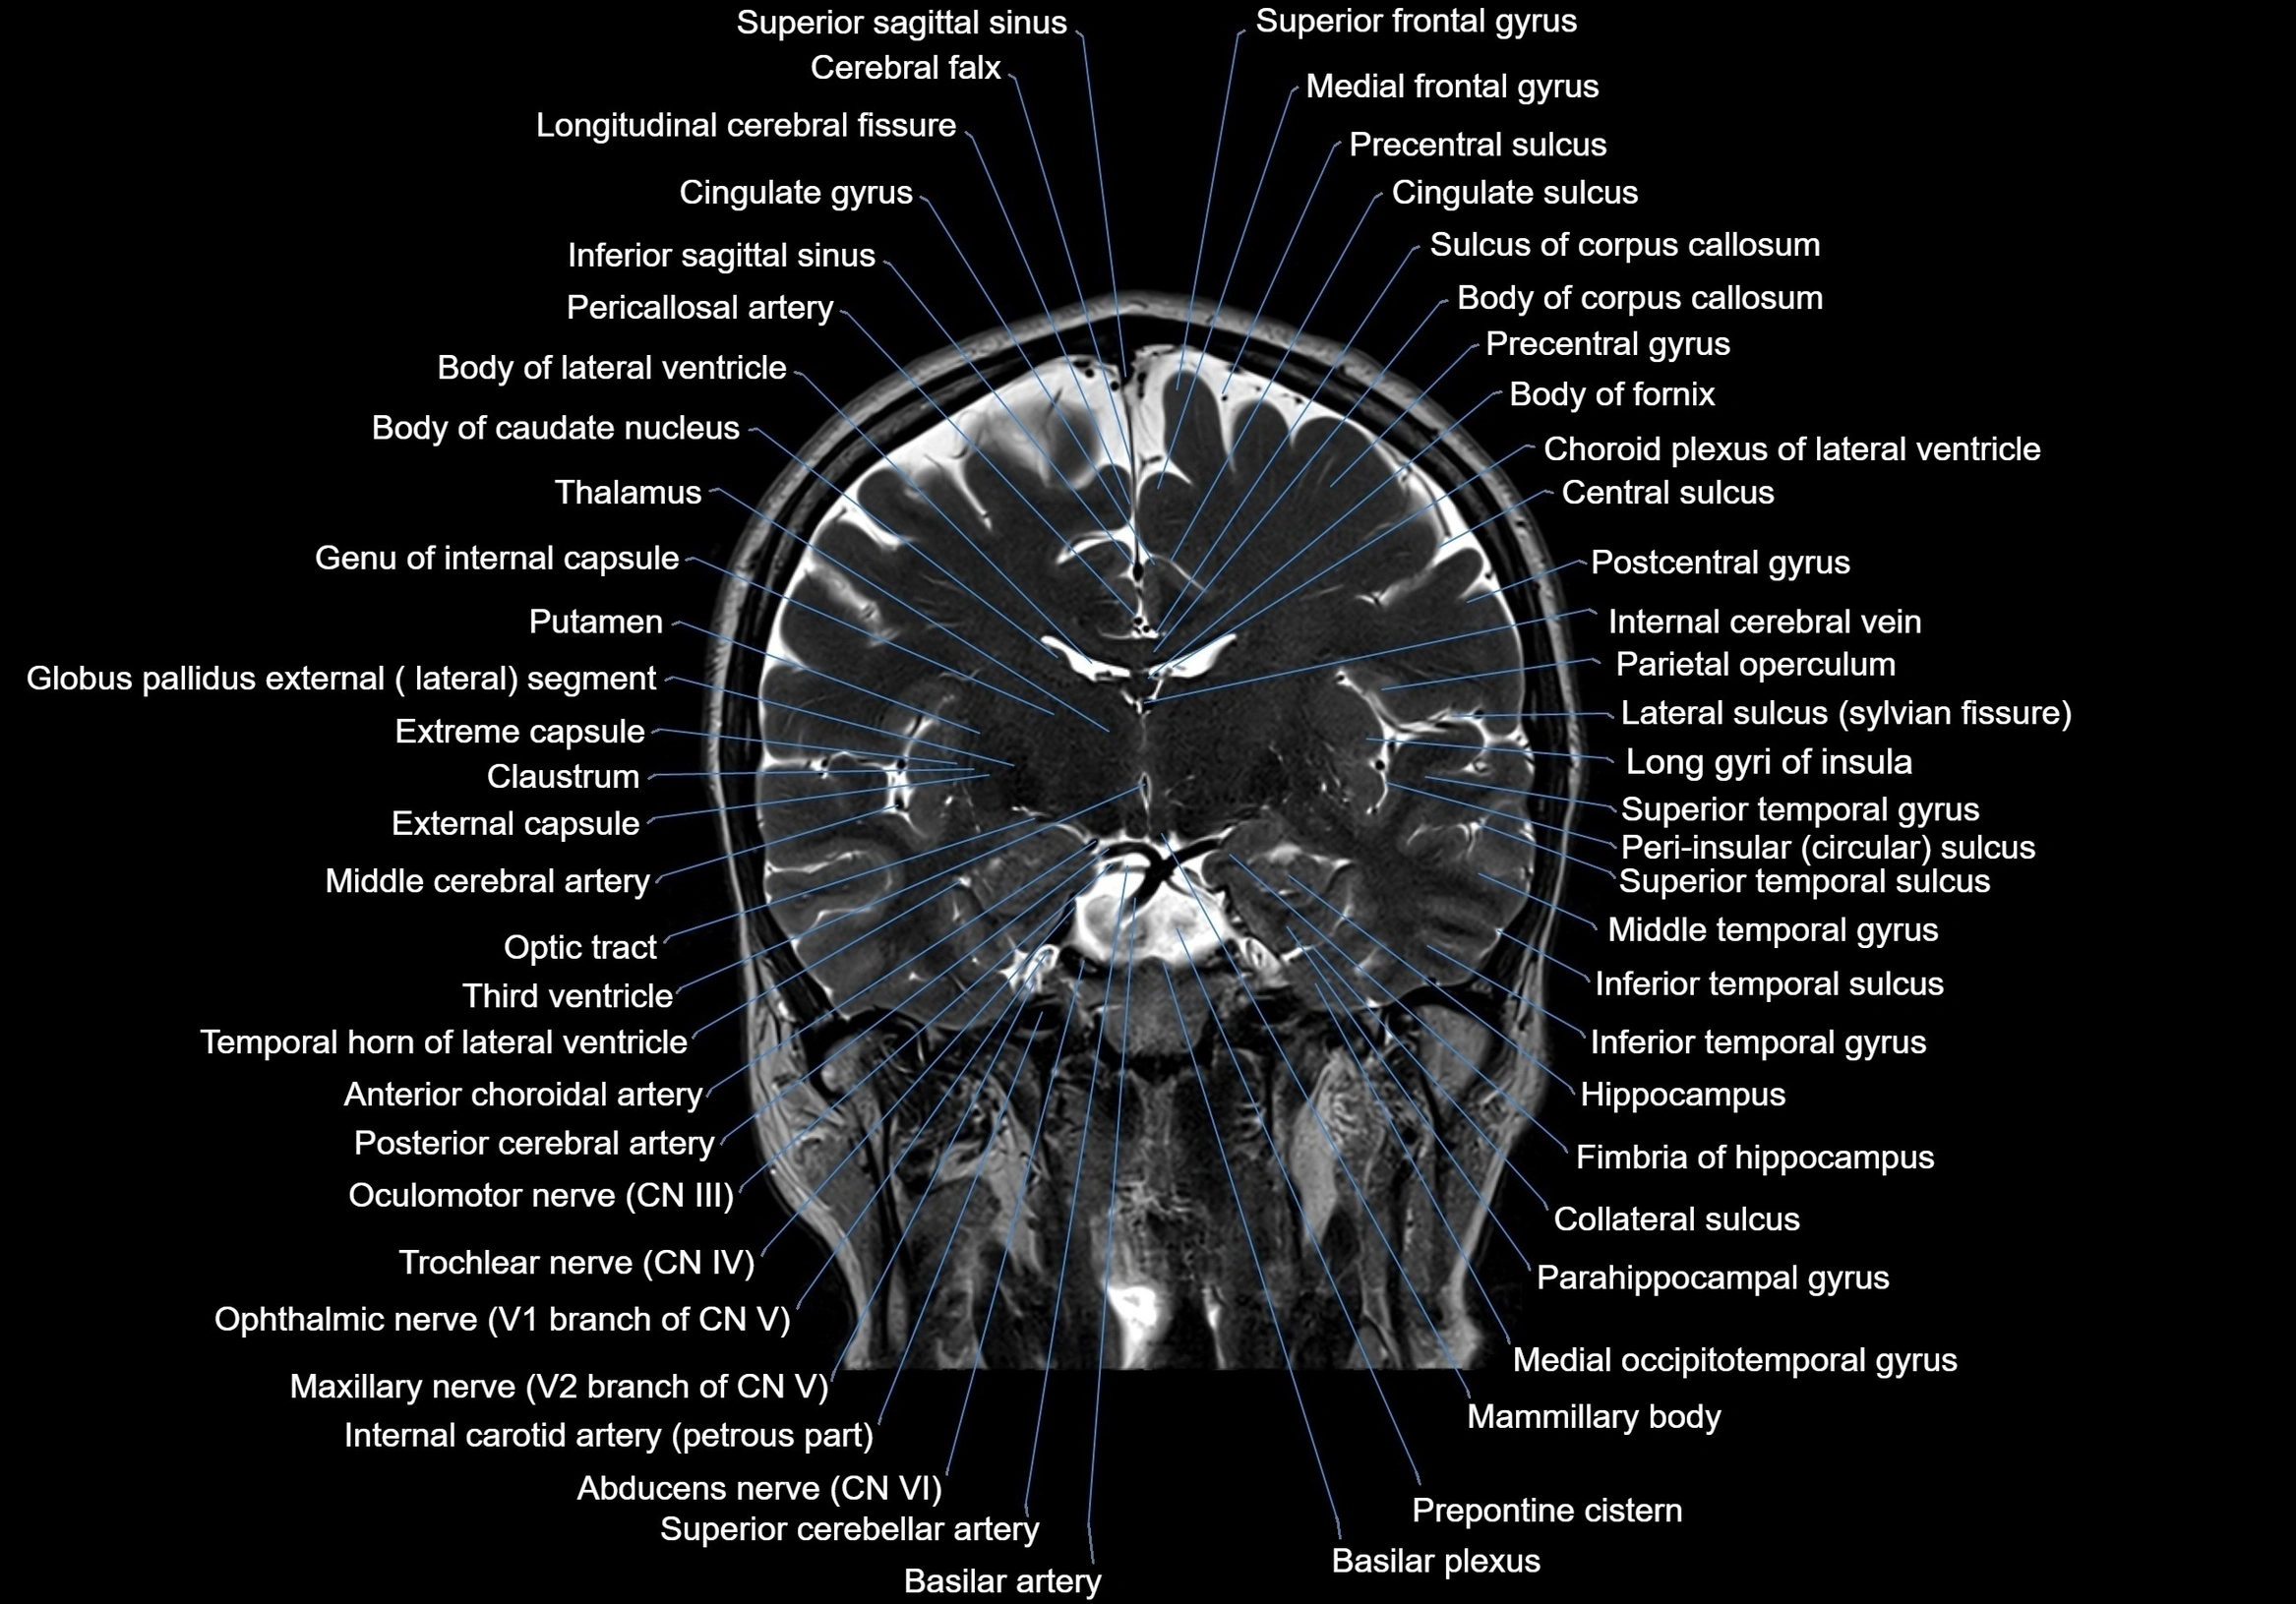

MRI images